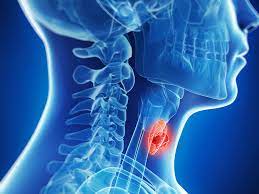

Value added benefits of the Tracheostomy:

Ø Doctor consultation charges

Ø Lab tests and diagnostic charges

Ø Room charges inside hospital during the procedure

Ø Surgeon Fee

Ø Nursing charges

Ø Hospital surgery suite charges

Ø Anesthesia charges

Ø Routine medicines and routine consumables (bandages, dressings etc.)

Ø Food and Beverages inside hospital stay for patient and one attendant.